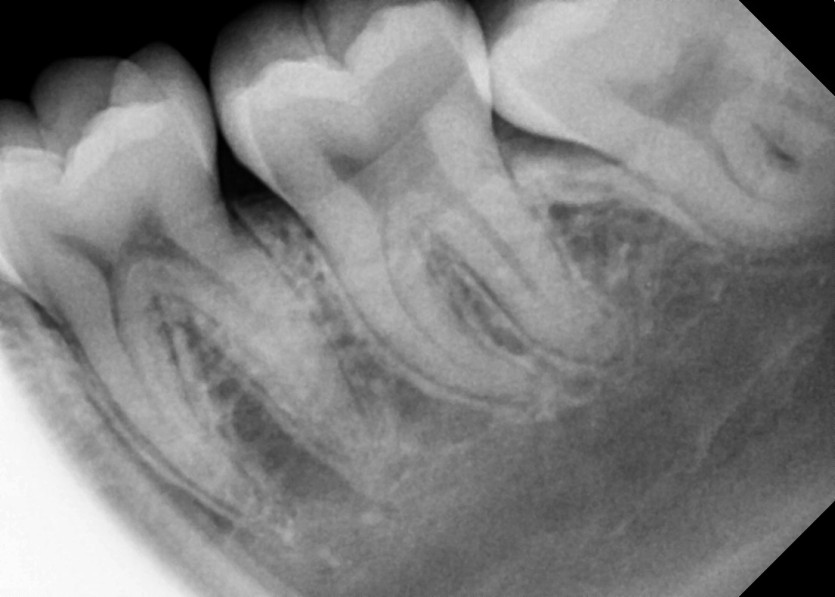

#28,38 사랑니 발치

구강 외과 전문의가 당일 발치했습니다.